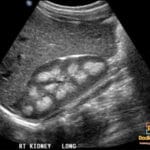

- US: Shows the “keyhole sign” (dilated posterior urethra and bladder), bladder wall thickening, hydroureteronephrosis, and potentially oligohydramnios in the prenatal setting.

- Vesicoureteral reflux (VUR) is present in approximately 50% of cases due to high intravesical pressures.

- Etiology/Pathophys: Maldevelopment of mucosal folds in the posterior urethra (Type 1 or Type 3/Cobb’s collar) creates an obstruction that leads to proximal urethral dilation, bladder wall hypertrophy/trabeculation, and upstream hydroureteronephrosis.